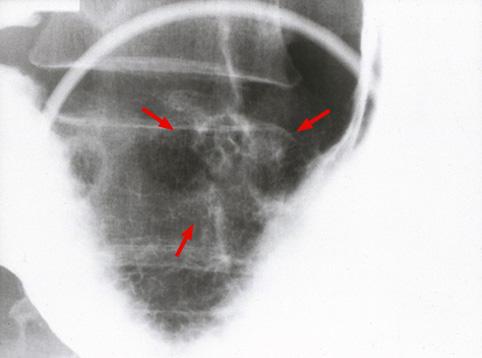

clasificación del pacienteTumor Epitelial Maligno/Adenocarcinoma

parte(separada por órganos)estómago(región)/ángulo

método de exámenRayos X

clasificación ectoscópica de tumoresTipo 0(tipo superficial)/Tipo IIc(IIc)

diámetro mayor del tumor15 - 19

grado de penetraciónm